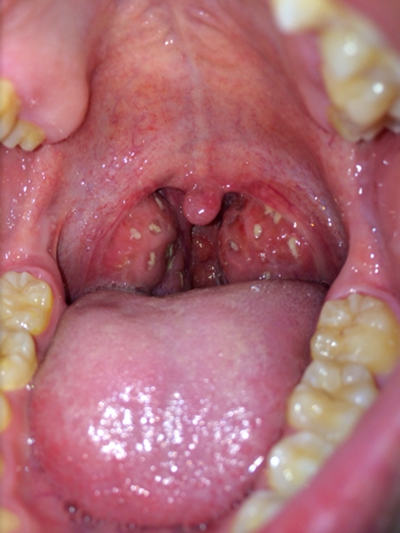

食道炎的症狀圖 (9)